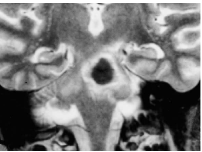

Складають 10-12% всіх випадків інсульту. Ключовою ознакою є швидке прогресування неврологічного дефіциту; великі за розміром крововиливи часто на початку дають розлади свідомості (коми). Характер і важкість неврологічного дефіциту залежить від локалізації та розмірів гематоми. Найбільший ризик крововиливів мають люди з неконтрольованою гіпертензією (утворення мікро аневризм Шарко-Башара). Інші причини: амілоїдна ангіопатія (у людей, старших 70), пухлини, коагулопатії та вживання антикоагулянтів, аневризми та судинні мальформації, зловживання алкоголем та наркотичними речовинами, травма та крововилив у зону мозкової ішемії. Діагноз встановлюється на КТ та МРТ. Хірургічне лікування, як терапія, що врятовує життя, показана при великих лобарних супратенторііальних та мозочкових гематомах, які звичайно порушують свідомість та спроможні викликати дислокацію мозку.

Гіпертензивні геморагії найчастіше зустрічаються в ділянці базальних гангліїв, таламуса, мозочка та в Варолієвому мосту. Лобарними називають геморагії, що локалізуються у півкулях мозку, але не охоплюють базальних гангліїв та таламуса (аневризми, мальформації, амілоїдна ангіопатія, геморагічний діатез внаслідок застосування антикоагулянтів, кокаїнова чи амфетамінова наркоманія; внутрішньовенне вживання героїну часто ускладнюється септичним ендокардитом з розвитком септичного емболізму та мікотичних мозкових аневризм).